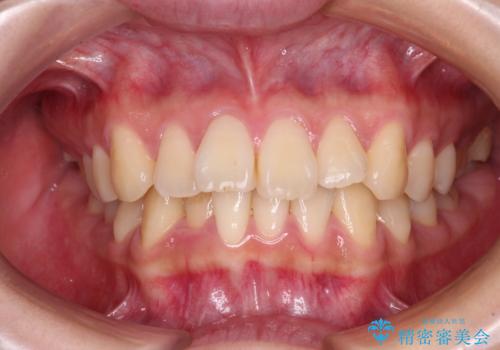

- 前歯の捻れを気にして来院された患者様です。

上顎前歯が捻れて前方に飛び出しており、下顎前歯もそれに沿うようにデコボコとなっていました。

IPR(歯と歯の間を削る処置)によりスペースを獲得して下顎前歯のデコボコを改善し、上顎前歯は下顎前歯と接する位置にまで引っ込めるように設定し、インビザラインにて矯正治療を行うこととしました。